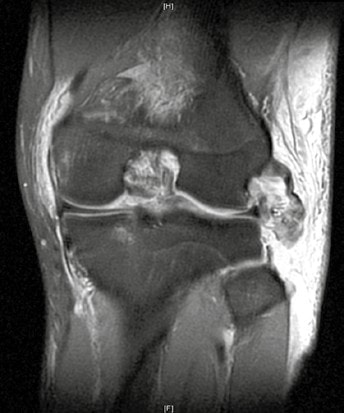

Die subakute Phase dauert bis zum Ende der dritten Woche, da in diesem Zeitraum die Heilungsvorgänge einsetzen. Therapeutisch stehen in dieser Phase die Rekonstruktion, Naht oder Augmentation der Bänder, des Streckapparates und ggf. die Therapie intraartikulärer Begleitverletzungen (Meniskus) im Vordergrund. Daher sollte unter diagnostischen Gesichtspunkten schnell eine MRT erfolgen, um diese Verletzungen näher zu charakterisieren. Die MRT erlaubt dabei nicht nur eine Klassifikation der Knieluxation, sondern auch eine detaillierte Beschreibung der Bandläsion (intraligamentär, Avulsionsverletzung) sowie der intraartikulären Begleitschäden (Abb. 3).